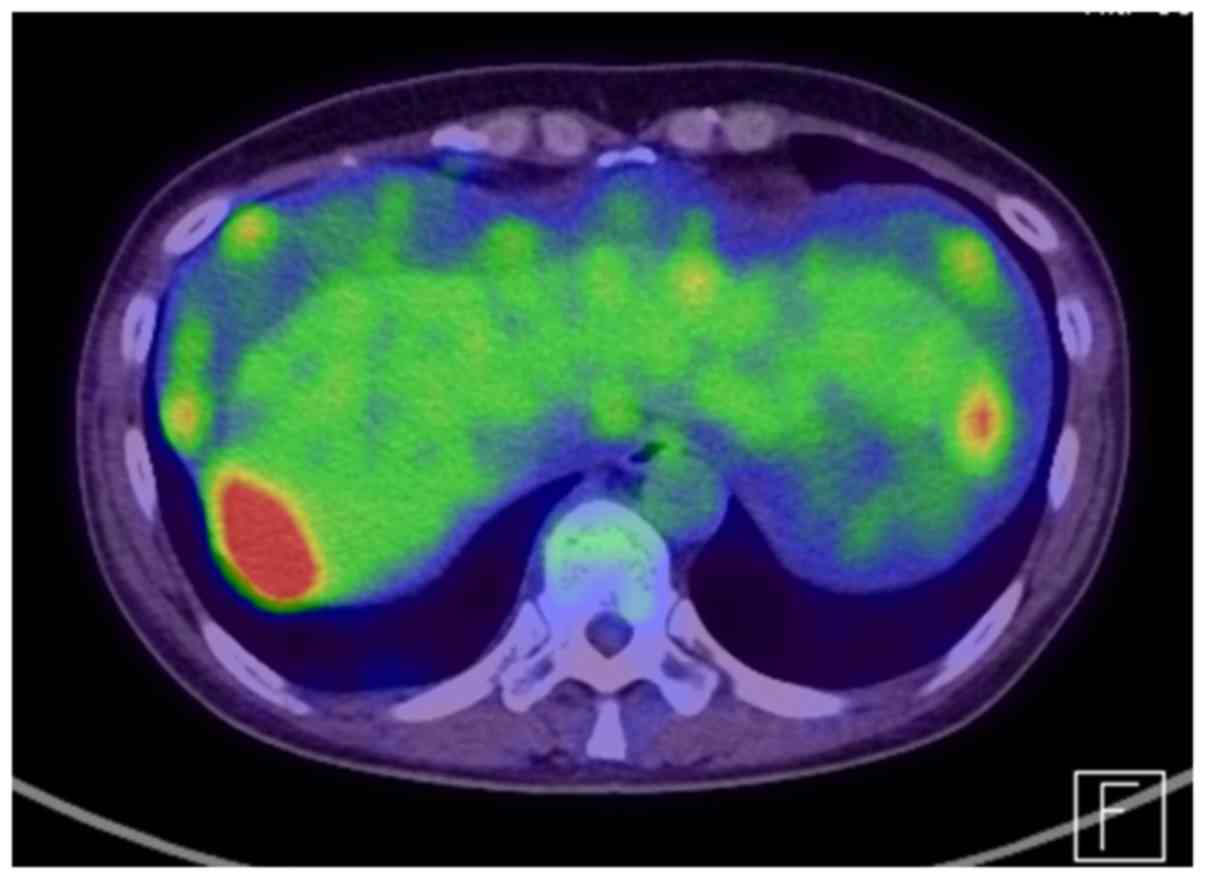

High-grade serous ovarian cancer 3 years after bilateral salpingectomy: A case report

Although epithelial ovarian cancer commonly originates from the ovarian surface epithelium and/or ovarian inclusion cysts, it was recently proposed that high‑grade serous ovarian cancer (HGSC) develops from the fallopian tubes. In our department, we encountered a case of HGSC that contradicts the hypothesis of a tubal origin for HGSC. A 51-year-old postmenopausal woman had undergone hysterectomy, left oophorectomy and bilateral salpingectomy for uterine myoma. Three years later, the patient was diagnosed with stage IV ovarian cancer and underwent primary debulking surgery. The pathological examination revealed HGSC, although there was no evidence of serous tubal intraepithelial carcinoma or any other type of cancer in the previously resected left ovary and bilateral fallopian tubes. Moreover, p53 overexpression was not detected in the right ovarian cancer specimen, while paired box gene 8, a marker of fallopian tube epithelium, was highly expressed. Therefore, HGSC may develop from an inclusion cyst with metaplasia of from the ovarian surface epithelium.

Figure 1

Figure 2